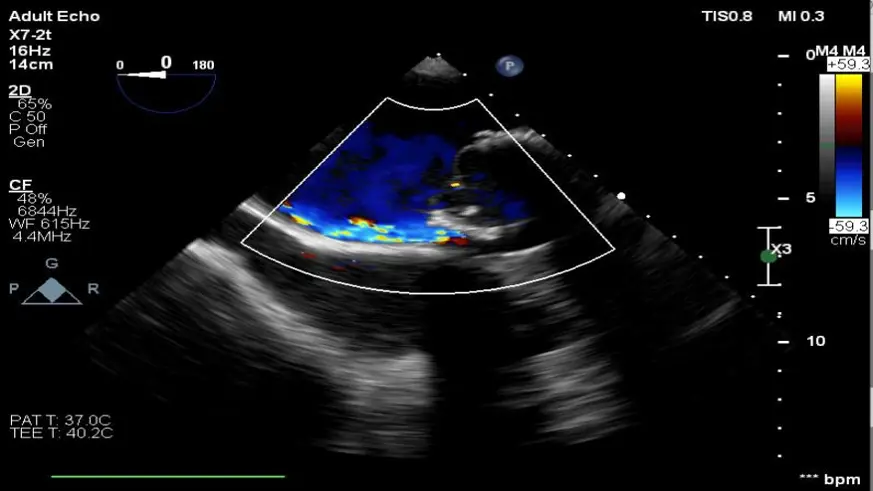

Hastanede yapılan, “Balıkesir’de ilk” nitelikli işlemlerin bir yenisi de Kardiyoloji Anabilim Dalı bünyesinde girişimsel kardiyoloji ile gerçekleştirilen paravalvüler kaçak kapatılması işlemi oldu.

Daha önce kalp kapakçığı değişim ameliyatı olan hastada takılan kapağın kenarından ayrılmasıyla kan kaçağı (paravalvuler leak) meydana geldiğini belirten öğretim üyeleri, Kardiyoloji Anabilim Dalına başvuran hastaya, Türkiye’de sayılı kalp merkezinde yapılan ve önemli düzeyde cerrahi deneyim gerektiren paravalvüler kaçak kapatılması işlemi uygulandığını dile getirdi.

İşlemin sadece girişimsel kardiyologlar tarafından yapıldığının altını çizen öğretim üyeleri, işlem sırasında hastanın kalbi durdurulmadan ve göğüs kafesi kesilmeden, kasığından girilerek yapay kalp kapağındaki kaçağın ameliyatsız kapatıldığını söyledi.